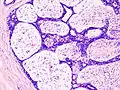

| Histopathologic image of breast fibroadenoma. Core needle biopsy. H&E stain. | |

Fibroadenoma of the breast is a benign tumor composed of a biplastic proliferation of both stromal and epithelial components.[12][13] This biplasia can be arranged in two growth patterns: pericanalicular (stromal proliferation around epithelial structures) and intracanalicular (stromal proliferation compressing the epithelial structures into slit-like spaces).

These tumors characteristically display hypovascular stroma compared to malignant neoplasms.[2][14][9] Furthermore, the epithelial proliferation appears in a single terminal ductal unit and describes duct-like spaces surrounded by a fibroblastic stroma. The basement membrane is intact.[15]

Fibroadenoma histology (H&E). The image demonstrates intracanalicular morphology (bottom left) and pericanalicular morphology (top right)

Histopathologic image of breast fibroadenoma. Core needle biopsy. Hematoxylin & eosin stain.

Histopathologic image of breast fibroadenoma showing proliferation of intralobular stroma compressing and distorting the epithelium. H&E stain.